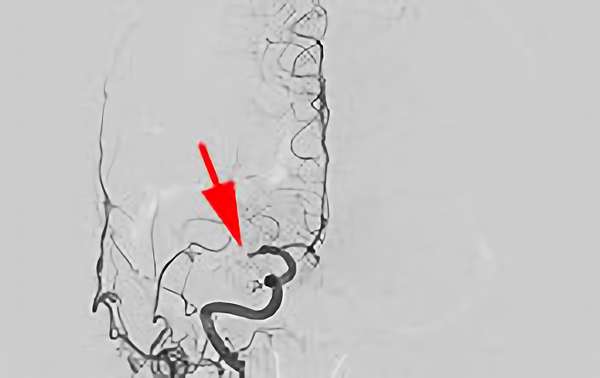

脳動静脈奇形

No.893 手術前

No.893 手術中